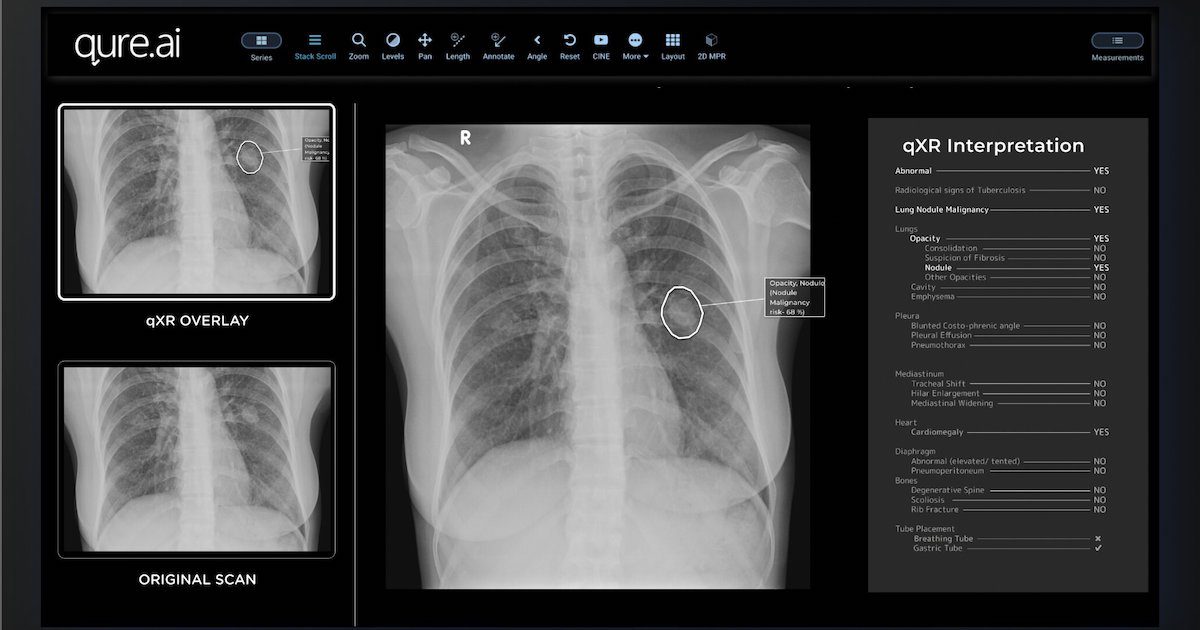

Mylab leverages Qure.ai's tech to enhance TB screening

Mylab leverages Qure.ai’s tech to enhance TB screening

Indian biotech company Mylab Discovery Solutions is integrating Qure.ai’s AI technology into its upcoming x-ray device for screening tuberculosis.According to a press statement, MyBeam is a compact, lightweight device equipped with high-frequency technology for detecting TB. It will be powered by Qure.ai’s deep-learning software qXR to analyse chest x-ray images and identify TB within a minute.

India is one of the biggest contributors to global TB cases, accounting for 26% of the total global count and 34% of all TB deaths.

By leveraging technological innovation, both Mylab and Qure.ai aim to support the Indian government’s goal of eliminating TB by 2025. Their integrated…